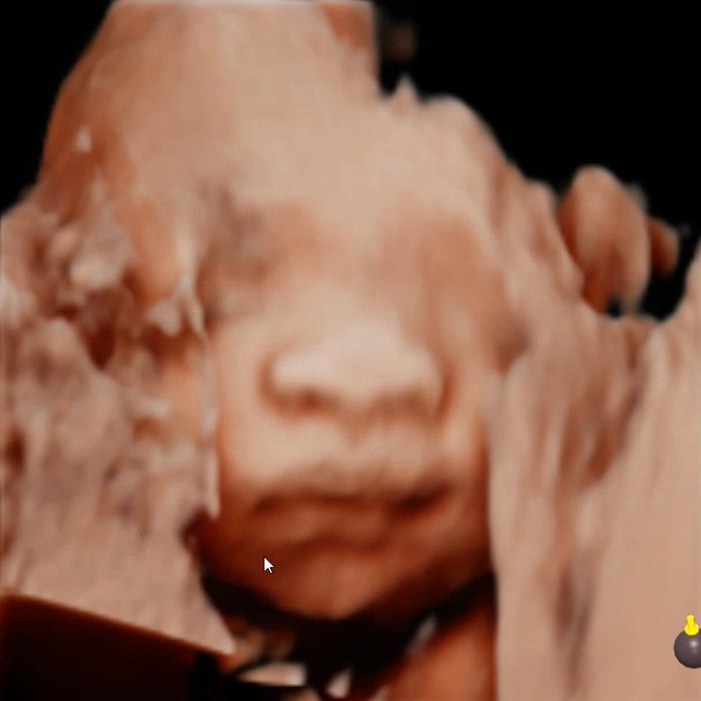

임신 27주차 입체 초음파 얼굴 임당 검사 재검 식단 일기

27주 임신 일기 저희 산부인과에서는 4D 입체 초음파 시기와 임당 검사 시기를 임신 26주로 말씀하셨는데...